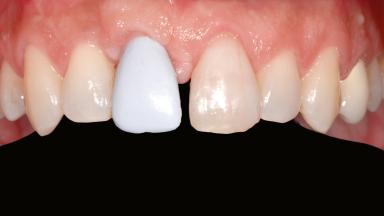

Staged bone augmentation of the alveolar ridge is indicated whenever a proposed implant site is deficient and will not support implant placement with simultaneous grafting. This is particularly true of healed sites presenting with facial flattening of the ridge. Since primary stability cannot possibly be achieved in this situation, it is recommended to use a staged approach with guided bone regeneration (GBR) for correct three-dimensional placement of the implant. In the anterior maxilla, staged GBR procedures are conducted not only to provide adequate bone volume for implant placement but also to restore a proper and stable contour of the orofacial ridge for improved long-term esthetics. A case is presented that demonstrates the technique for single-tooth replacement utilizing a staged approach with a particulate grafting material. A 50-year-old man whose tooth 11 was missing presented for consultation to the Center for Implant Dentistry in January 2010.